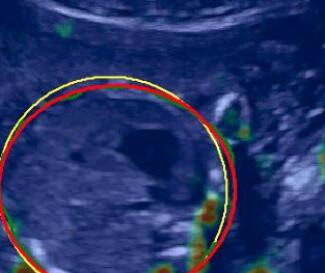

We propose a novel method based on convolutional neural networks (CNNs) to automatically estimate pixel-wise confidence maps of acoustic shadows in 2D US images. Our method learns an initial latent space of shadow regions from images consisting of multiple anatomies and with global image-level labels (“has shadow” and “shadow-free”), e.g. Fig. 1(a). The basic latent space is then estimated by learning from fewer images of a single anatomy (fetal brain) with coarse pixel-wise shadow annotations (approximately of the images with global image-level labels), e.g. Fig. 1(b). The resulting latent space is then refined by learning shadow intensity distributions using fetal brain images so that the latent space is suitable for confidence estimation of shadow regions. By using shadow intensity information, our method can detect more shadow regions than the coarse manual segmentation, especially relatively weak shadow regions.

We propose a shadow-seg module to extract generalized shadow features for a large range of shadow types in fetal US images under limited weak manual annotations. Since shadow regions have different shapes, various intensity distributions and uncertain edges, the pixel-wise annotation of shadow regions is time consuming and relies heavily on annotator’s experience (e.g. various annotations in Fig. 1(b)). This generally results in manual annotations of limited quantity and quality. Compared with pixel-wise shadow annotations, global image-level labels (“has shadow” and “shadow-free” in our case) are easier to obtain, and shadow images with global image-level labels can contain a larger variety of shadow types. Therefore, we use a shadow-seg module that combines unreliable pixel-wise annotations and global image-level labels as weak annotations.The proposed shadow-seg module contains two tasks, (1) shadow/shadow-free classification using image-level labels, and (2) shadow segmentation that uses few coarse pixel-wise manual annotations ( of the global image-level labels). Shadow features can be extracted during simple shadow/shadow-free classification and subsequently optimized for the more challenging shadow segmentation task. In our case, shadow features extracted by the classification network cover various shadow types in a range of anatomical structures. These shadow features become suitable for the shadow segmentation after being optimized by a shadow segmentation network.

This data set comprises 643 fetal brain images and has no overlap with the multi-class data set. Shadow regions in this data set have been coarsely segmented by two bio-engineering students using trapezoid-shaped segmentation masks for individual shadow regions.